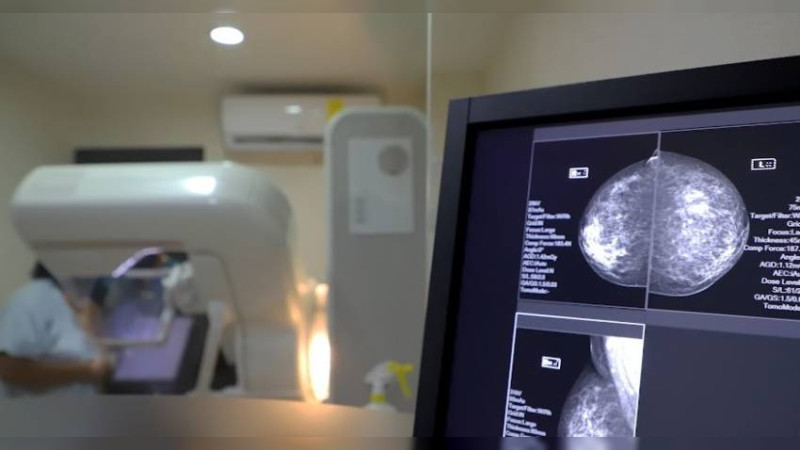

Morelia, Michoacán, 3 de agosto de 2024.- Gracias a las 22 mil 411 mastografías gratuitas realizadas por el sector salud a través de sus unidades fijas y móviles, durante lo que va de este 2024 se han logrado detectar 282 nuevos casos de cáncer de mama en etapas tempranas.

El sector salud exhorta a las michoacanas, a realizarse sus revisiones médicas de manera regular, una mastografía cada dos años a partir de los 40 años y cada año después de los 50, implementar hábitos de vida saludables, evitar consumo de alcohol y tabaco; así como mantener un peso adecuado.

El cáncer de mama es el que provoca mayor mortalidad entre las mujeres y cada vez se presenta con mayor frecuencia, por ello, la importancia de la detección oportuna a través de la mastografía (mujeres 40 a 69 años) y exploración mamaria a partir de los 20 años y la exploración clínica de mamá es de 25 a 39.